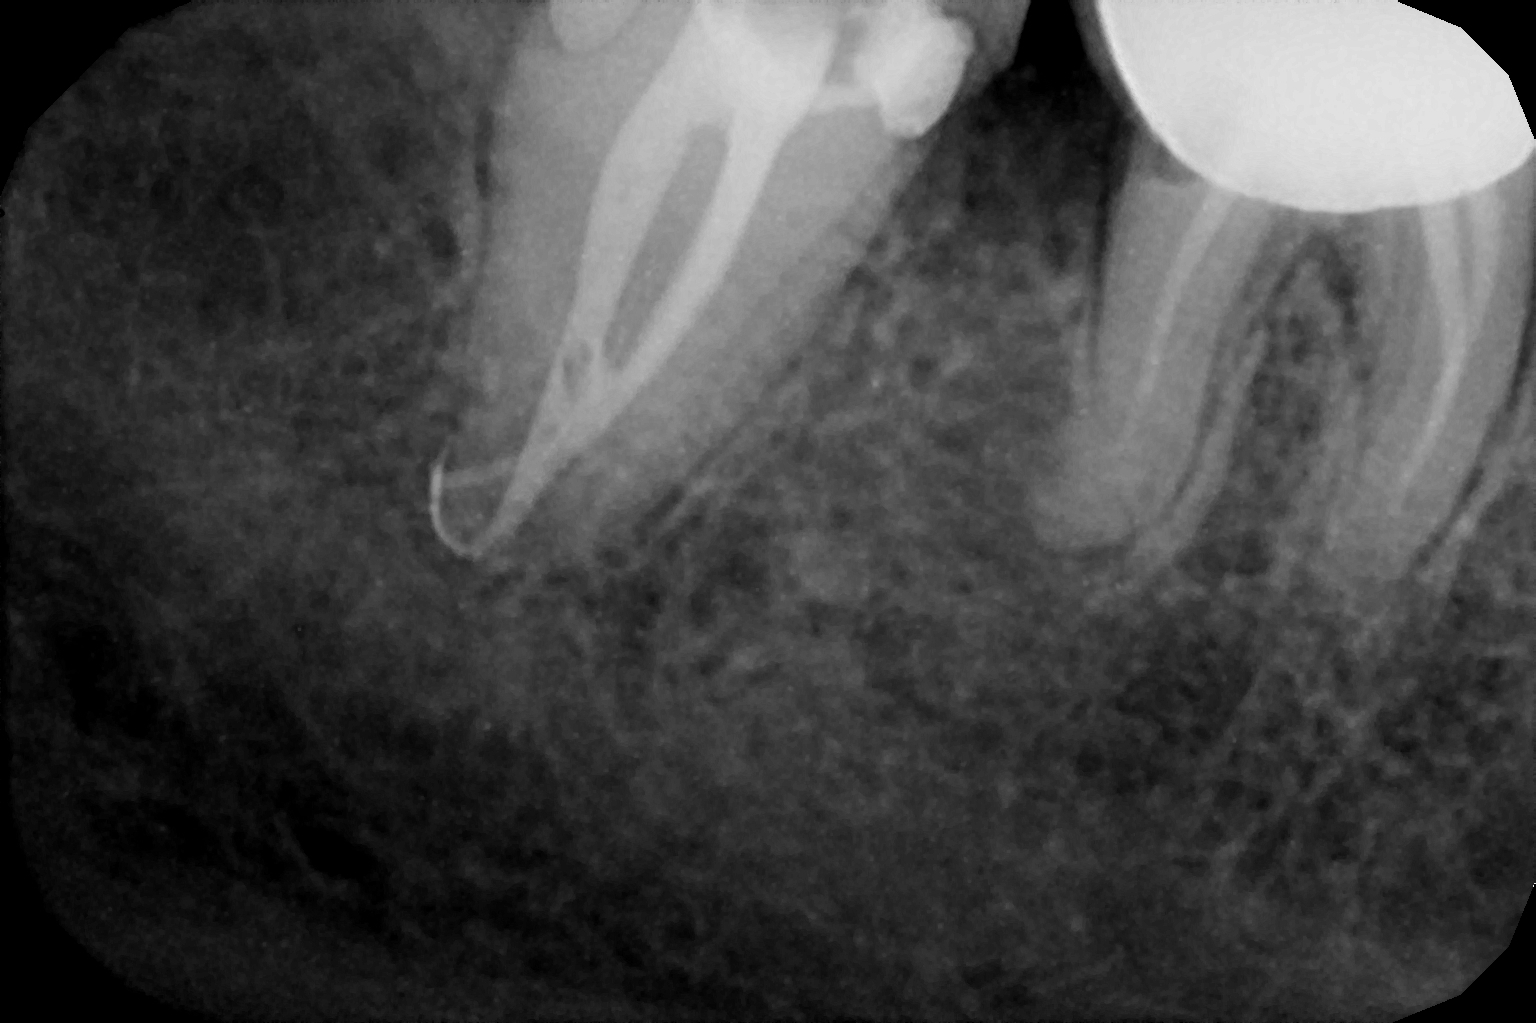

When the tooth is is sensitive to particularly hot and cold. When you cannot chew from that side or there is associated action of pain and swelling with same tooth, root canal treatment can save the tooth. For root canal treatment our clinic is equipped with state-of-the-art facility. We are following the protocol that is universally accepted and considered as a gold standard We are using rubber Dam for maximum possible cases. The root canal treatment is done under local anaesthesia that's why mostly it is painless . The rubber Dam isolation helps in proper irrigation and it provides much needed ease to the operating dental surgeon and the patient . The sealer and filling material are one of the Prime requisite of quality root canal treatment, it needs use of multiple X rays to really judge whether the results are acceptable or not. In older days root canal was just about cleaning the decade portion, removing the Pulp and filling it with biocompatible material but nowadays the root canal treatment it is very much advanced the precision is increased manifold. The materials and armamentarium that is required for efficient root canal have advanced in exclusion initial ways the the Abstract of all these things is the patients are getting great results after root canal treatment. Only the root canal is not sufficient to make a tooth functional again ,it needs use of Core buildup material and complete coverage Crowns according to the tooth position. During Covid19 time we have studied and implemented use of of high strength composites in our practice and the results of it are amazing many times it has saved tooth from being restored with crown. In some cases where the tooth is grossly carious we need a complete coverage crown. The materials and the Crown materials are are available in various price ranges. We prefer only the best of materials for our patients. We believe that to perform best treatment we need best of the armamentarium and best of the material for our patients who value and deserve the best of the treatment.